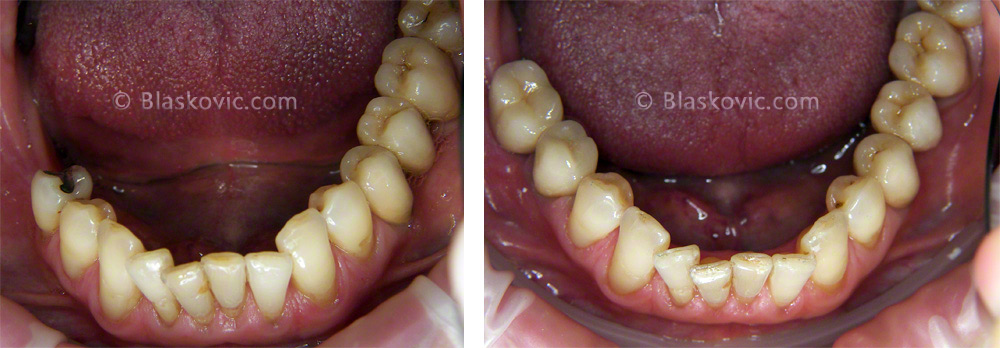

Gubitak donjih desnih kutnjaka, most nad implantatima